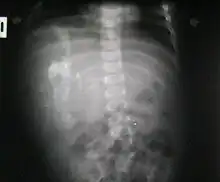

Ocurre en 1 de 1 000 000 nacimientos,[1][2] y se define como una masa fetiforme totalmente encerrada dentro del cuerpo del autósito o hermano desarrollado. Al extraerse, está envuelto en lo que parece un huevo de gallina, pero mucho más grande y extremadamente duro. El parásito, cuando es extraído y expuesto, tiene un color blanco. Una vez que se extrae, muere, ya que es un tejido totalmente dependiente de su hospedador. Al igual que en los gemelos parásitos, corazón y cerebro están ausentes o son muy rudimentarios. Puede estar más o menos organizado, con características muy variables, desde apenas una bola de tejidos hasta contener restos de pelo, hueso, manos con dedos y uñas y hasta piernas. La extirpación quirúrgica no presenta el menor problema dado que no pasan de ser tumores que pueden llegar a ser un potencial riesgo para su hospedador, debido a que se alimenta de este, representando para el hospedador una carga semiviva sin función en el organismo, y pueden llegar a malignizar.[3]